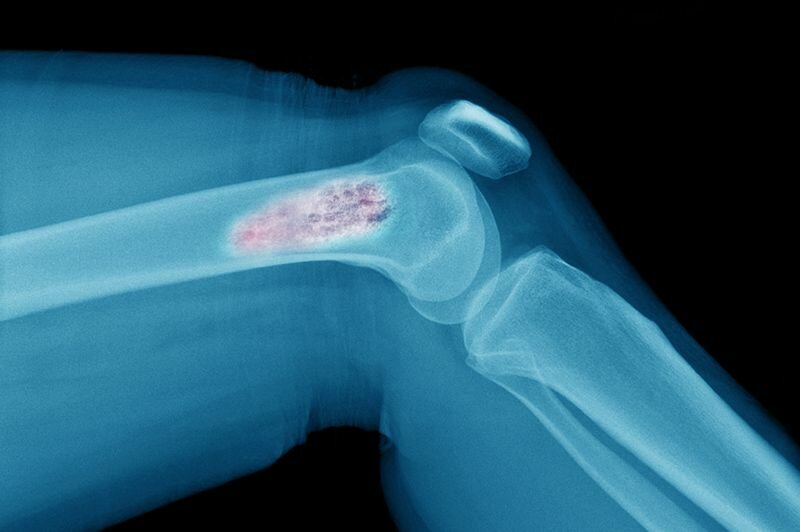

Саркомы костей: ранняя диагностика, лечение | ОкейДок | Яндекс Дзен

саркома